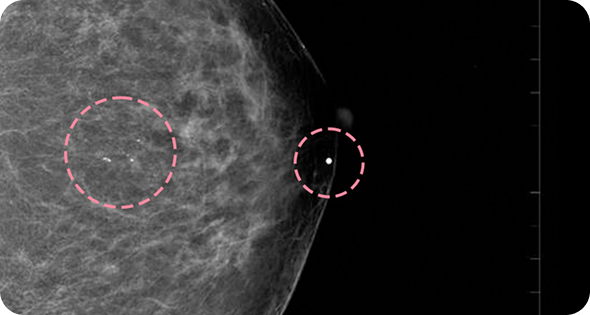

맘모톰시술 후 병리조직검사 결과 상피내암(조기 유방암) 초기로 진단되어 항암치료 없이 간단한 수술로 치료가 가능했습니다. 눈에 잘 띄지 않는 작은 병변까지 확인할 수 있었던 건, 맘모톰의 정밀한 조직검사 기능과 전문의의 정확한 판독이 있었기 때문입니다.